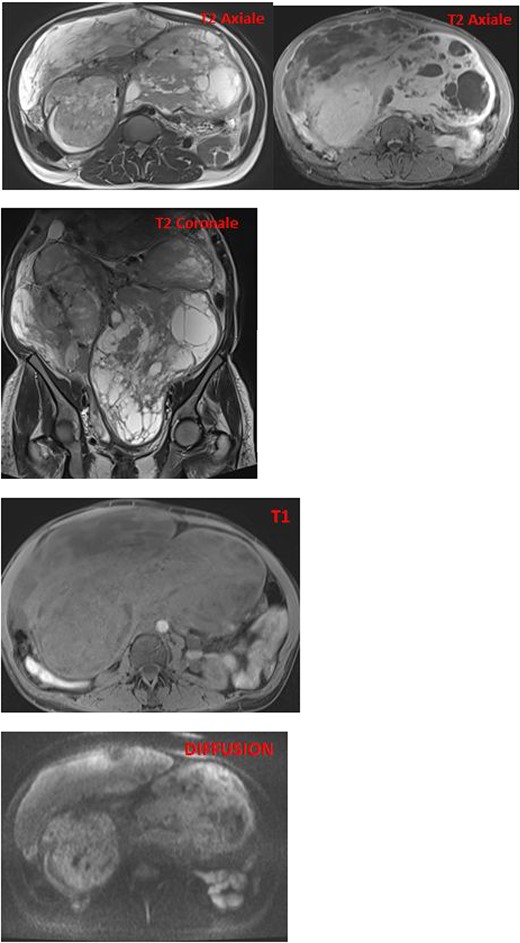

MRI images reveal an enlarged uterus with multiple myometrial formations exhibiting intermediate signal on T1 and T2, encompassing regions of hyperintensity on T2 and hypointensity on T1, enhanced homogeneously compared with the myometrium and without diffusion restriction, the most characteristic ones are classified as FIGO 6, FIGO 7, and FIGO 2–5, suggesting uterine leiomyomatosis with cystic degeneration.

The pathological and immunohistochemical examination suggested a smooth muscle mesenchymal tumor without signs of malignancy, raising the possibility of disseminated intravascular leiomyomatosis or a BML (Figs 4 and 5). The thoracic computed tomography (CT) indicated the presence of a mass in the inferior vena cava extending into the right atrium. Magnetic resonance imaging (MRI) confirmed uterine leiomyomatosis (Fig. 3). This explains the origin of the mass in the right atrium.

Exploring the inferior vena cava at its intra-abdominal portion was difficult because it was compressed by the uterine mass (Fig. 2). Following discussions and collaboration among vascular surgery, gynecology, anesthesiology, cardiothoracic surgery, and intensive care, the diagnosis of intravascular leiomyomatosis was confirmed.

CT and MRI are crucial for determining the size and shape of the uterus (Figs 2 and 3), confirming the myometrial origin of the mass, and specifying the extent of vascular involvement. This classification distinguishes four grades [1]:

On MRI, the appearance of endovascular material depends on the quantity of smooth muscle cells and fibrous tissue. Generally, it exhibits low to intermediate signal on T1 and low signal on T2 [6] (Fig. 2).